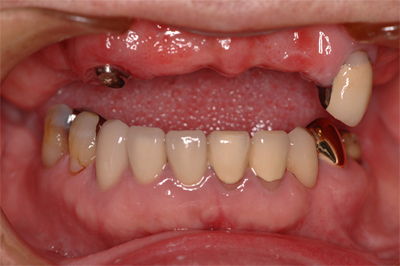

入れ歯の治療例

当院では、患者様が少ないご負担で安心して食事ができるよう、保健治療で入れ歯をお作りしています。同じ入れ歯を10年20年使っていただいている患者様も多くいらっしゃいます。

装着前

装着後

16年間使っている義歯